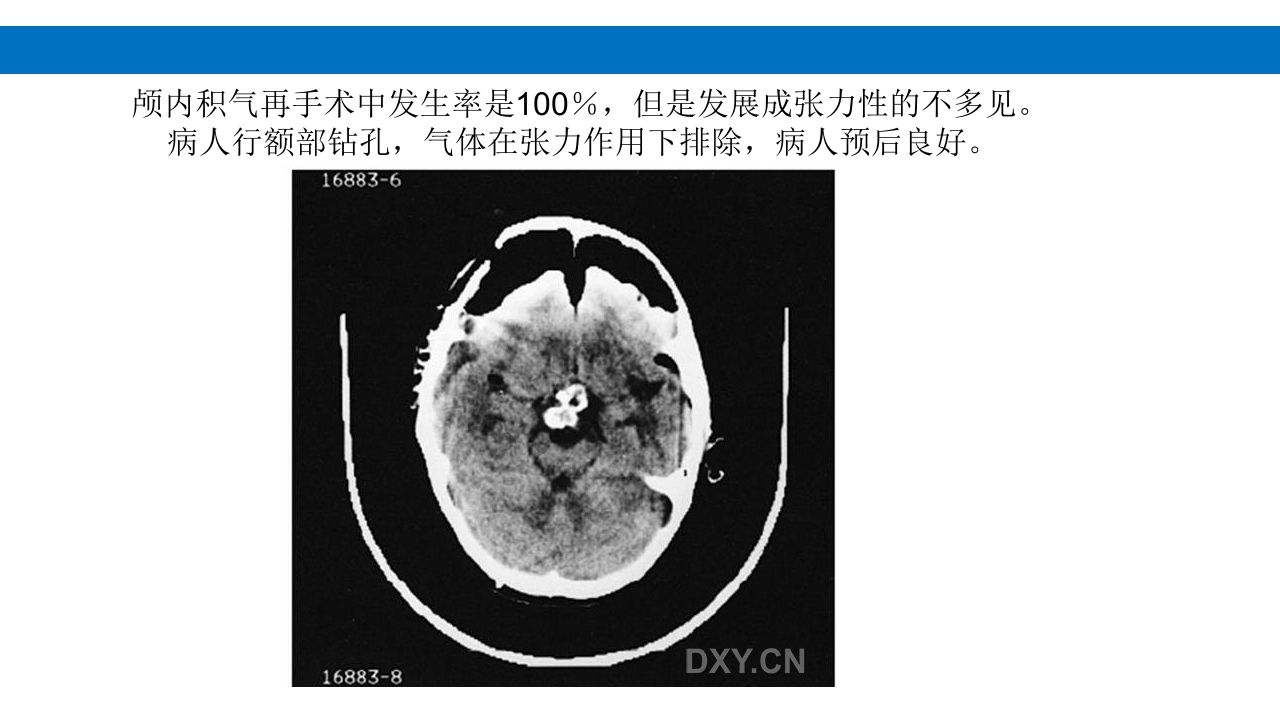

颅脑损伤的并发症及后遗症 讲解人:xxx 20XX年x月x日 1.颅骨骨髓炎 病因:为头皮软组织、中耳、乳突和副鼻窦等处炎性感染而经导 血管侵入颅骨内或颅脑开放伤感染所引起,亦可由菌血症后发生 的细菌栓子由血运转移至颅骨内。 影像学表现: 头部CT: 1.表现为不规则的蜂窝状骨质破坏区,主要位于板障,亦可累 及内外板。 2.破坏区内可见高密度的米粒状细小的高密度死骨。 3.周边可见骨质硬化增生,颅板外无骨膜反应。 4.局部的头皮可见软组织肿胀。 头部MRI: 由于受累部位细胞成分和水量增多,T1WI为低信号, T2WI为高信号,急性期边界不清,慢性期病灶局限, 边界清晰。MRI显示骨质破坏没有CT效果好。 治疗: 除应用抗菌药物控制感染外,当感染局限或已有死骨形成后, 应行手术切除感染...